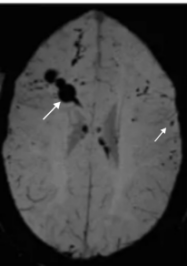

磁敏感加权成像(SWI): 这是最敏感的序列!它能把微小的出血点放大显示为一片片黑色的“墨点”,清晰揭示损伤的范围和严重程度。

图片说明:男,37Y,SWI可见脑内多发点片状低信号(白色箭头所示)。